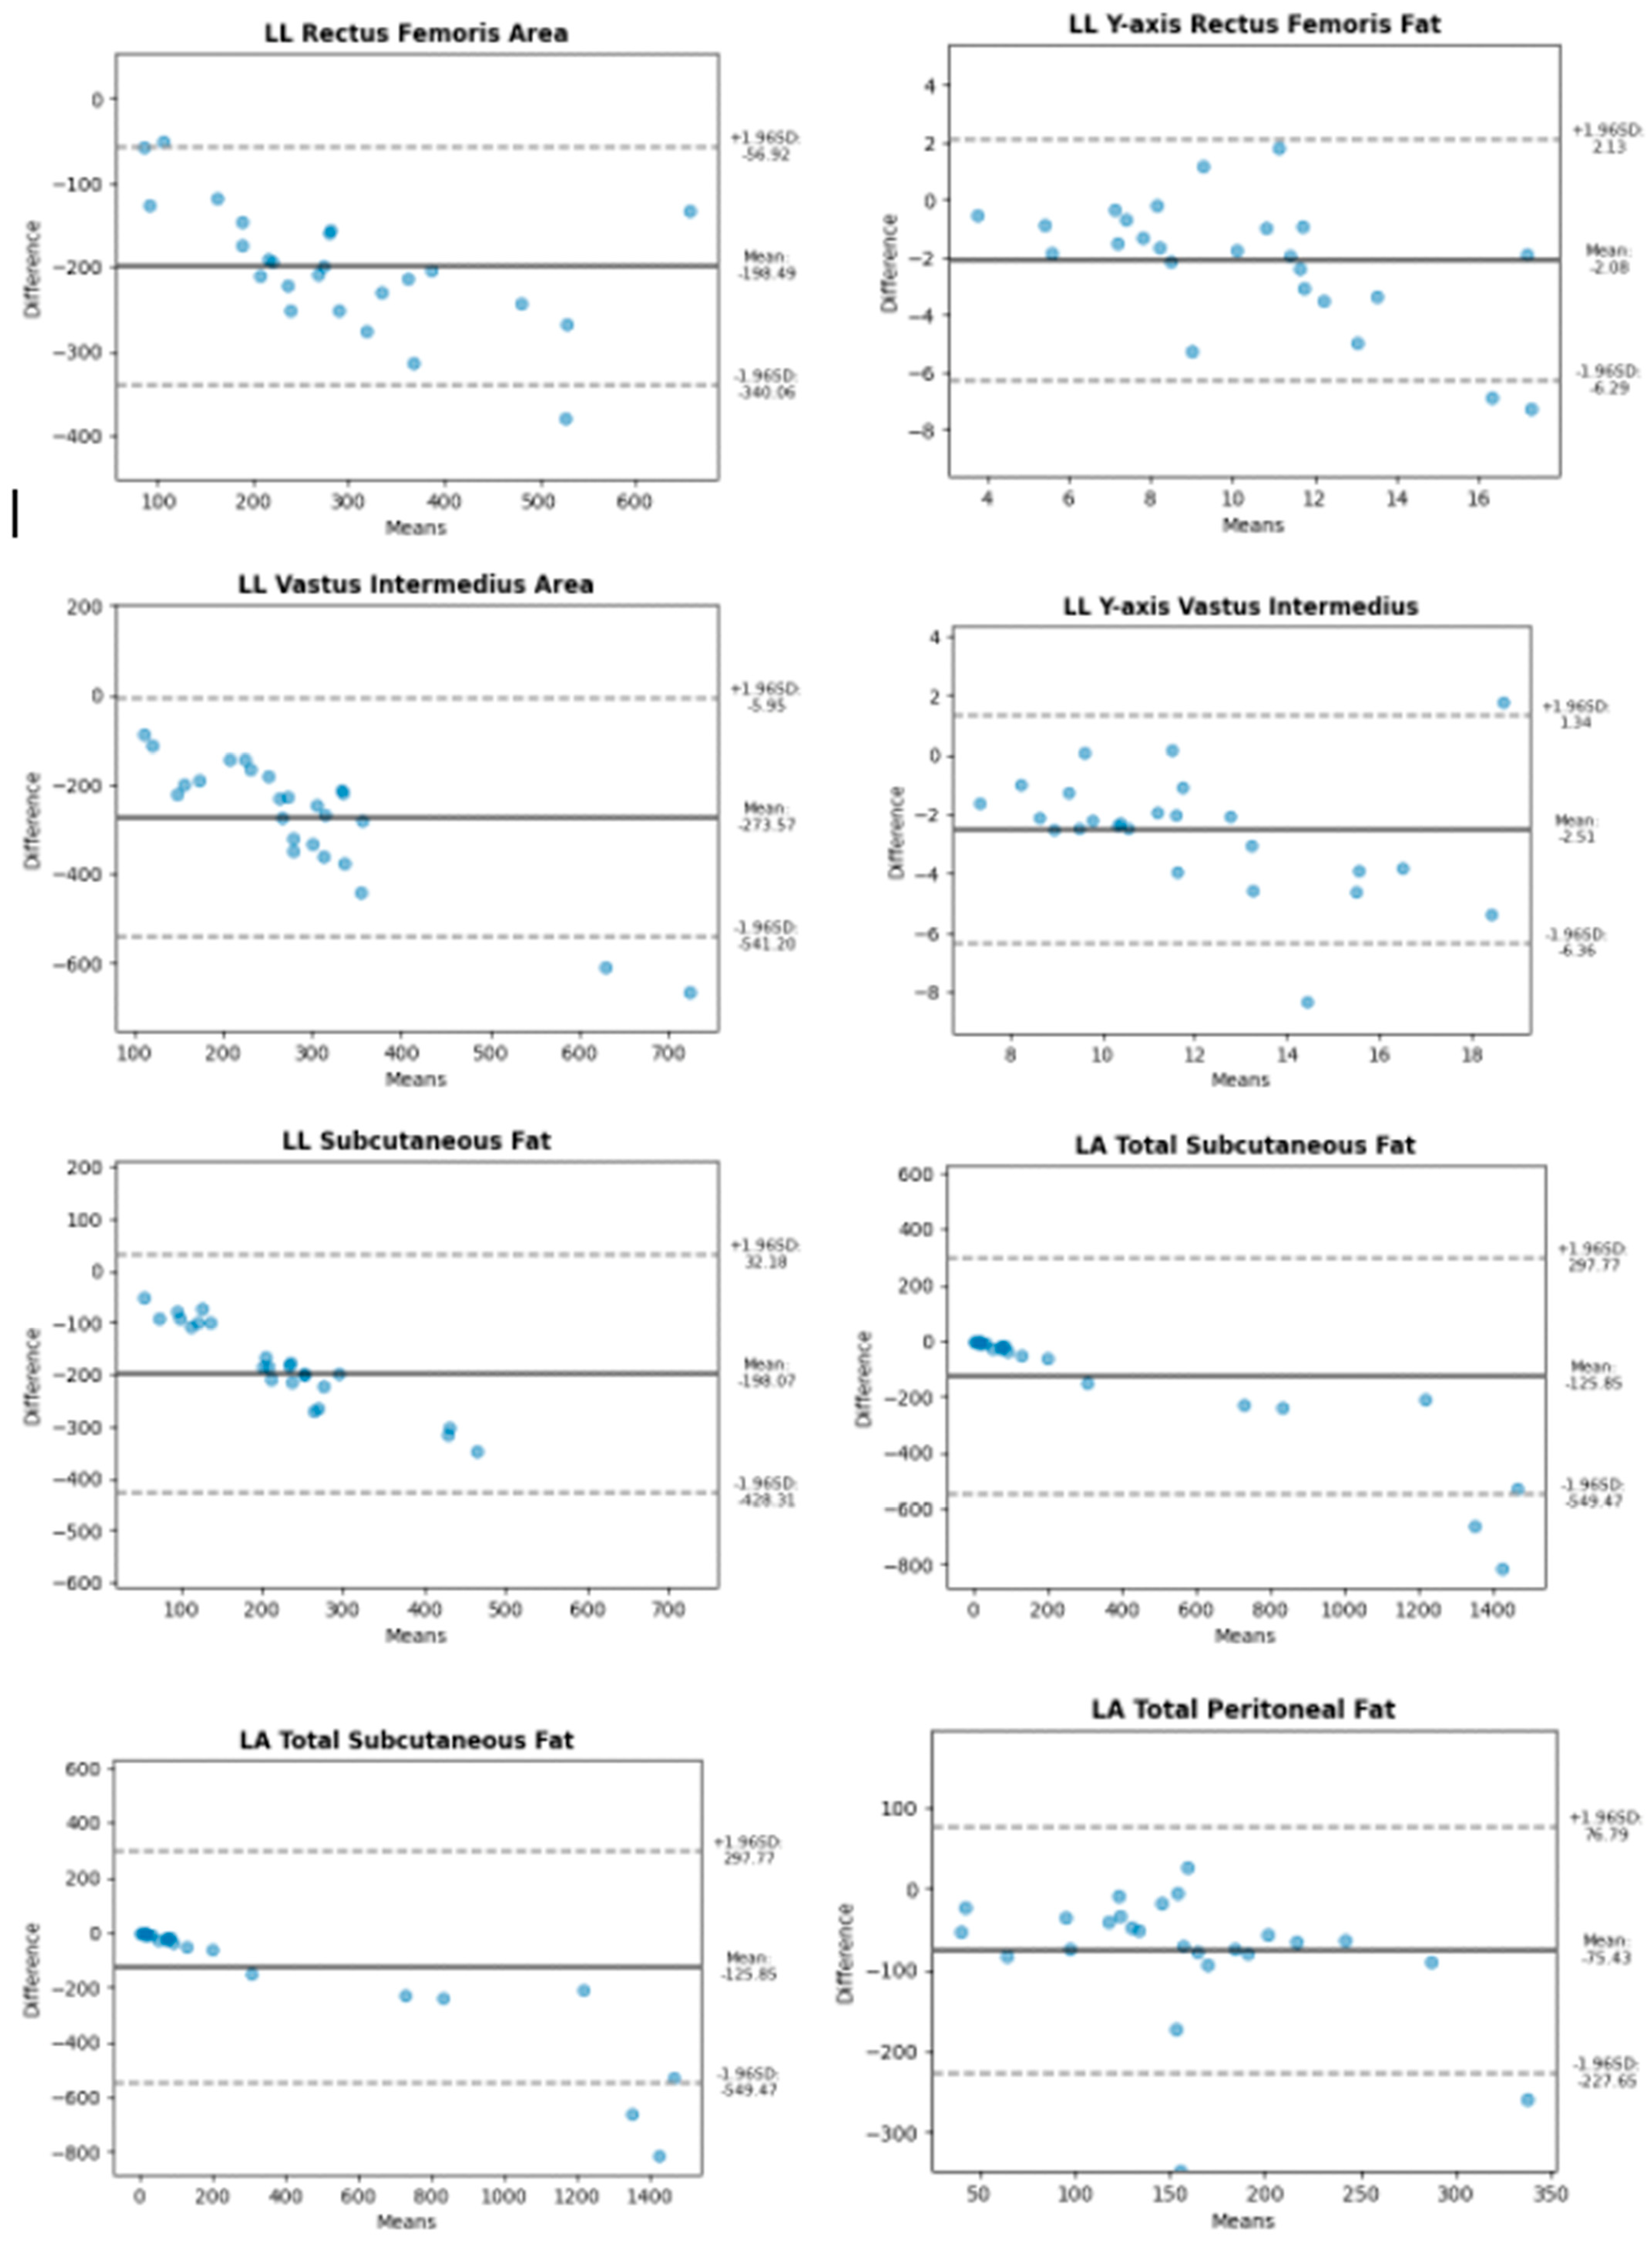

3. Results

| Abdomen | Longitudinal | Subcutaneous fat, total | 71.42 |

| Subcutaneous fat, superficial | 68.77 | ||

| Peritoneal fat | 63.0 | ||

| Transversal | Subcutaneous fat, total | 54.3 | |

| Subcutaneous fat, superficial | 55.65 | ||

| Peritoneal fat | 51.02 | ||

| Leg | Transversal | Y-axis Rectus femoris | 78.73 |

| Rectus femoris area | 28.09 | ||

| Y-axis Vastus intermediate | 81.65 | ||

| Vastus intermediate area | 43.31 | ||

| Longitudinal | Subcutaneous fat | 40.82 | |

| Y-axis Rectus femoris | 83.85 | ||

| Rectus femoris area | 46.33 | ||

| Y-axis Vastus intermediate | 81.39 | ||

| Vastus intermediate area | 36.52 |